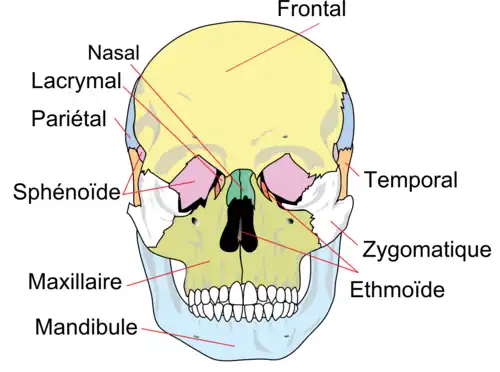

Le maxillaire (anciennement maxillaire supérieur) est un os pair et asymétrique participant au massif facial. On en dénombre deux, accolés l'un à l'autre et symétriques par rapport à la ligne médiane[1].

Situation

Il compose, avec son homologue, l'arcade dentaire supérieure (qui s'articule avec l'arcade dentaire inférieure par l'intermédiaire des dents), la partie inférieure de l'orbite osseuse, la face latérale des fosses nasales ainsi que le palais osseux. Il s'articule avec tous les os du massif facial supérieur : os palatin, os zygomatique, os lacrymal, cornet nasal inférieur, nasal et vomer. Concernant les os du crâne, le maxillaire s'articule avec l'os frontal et l'os ethmoïde.

- le processus frontal qui s'articule avec l'os lacrymal, le nasal, le frontal (bord nasal) et l'ethmoïde ;

- le processus palatin qui sépare les cavités nasales de la cavité orale ;

- le processus alvéolaire, en forme d'arc, creusé en cavités recevant les dents ;

- le processus zygomatique, participant à la formation de l'arcade zygomatique.

Coupe sagittale para-médiane Les os du crâne

Les os du crâne